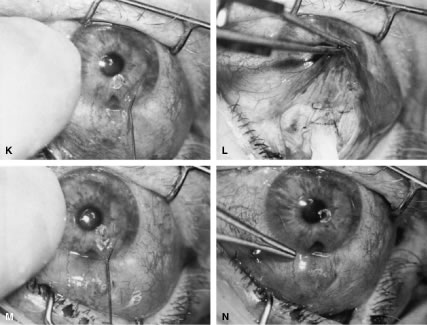

incision, or it can be coapted with the wet-field cautery.   Fig. 11. Fornix-based flap procedure. A. With a scissors or knife, the conjunctiva is incised as close to the limbus

as possible. B. The incision is widened. The surgeon uses forceps to stretch the tissue. The

scissors cut inferiorly so that no remnant of conjunctiva is left

on the globe. C. Tissue is separated from the globe by inserting the scissors with the

tips closed and then spreading them bluntly. D. Blunt dissection is continued until the sclera is cleaned adequately. Bleeding

from the cut conjunctival vessels is almost inevitable and usually

exceeds the bleeding that occurs when a limbus-based flap is raised. E. A radial cut at the edge of the peritomy will improve visualization of

the sclera and permit a neat closure of the conjunctiva. F. The cut edge of a fornix-based flap is pulled inferiorly and secured with

a 10-0 nylon purse-string suture. G. With large incisions, it usually is necessary to suture both edges to

ensure tight closure. (Spaeth GL. Glaucoma surgery. In Spaeth GL (ed). Ophthalmic Surgery: Principles

and Practice. Philadelphia: WB Saunders, 1990.) Fig. 11. Fornix-based flap procedure. A. With a scissors or knife, the conjunctiva is incised as close to the limbus

as possible. B. The incision is widened. The surgeon uses forceps to stretch the tissue. The

scissors cut inferiorly so that no remnant of conjunctiva is left

on the globe. C. Tissue is separated from the globe by inserting the scissors with the

tips closed and then spreading them bluntly. D. Blunt dissection is continued until the sclera is cleaned adequately. Bleeding

from the cut conjunctival vessels is almost inevitable and usually

exceeds the bleeding that occurs when a limbus-based flap is raised. E. A radial cut at the edge of the peritomy will improve visualization of

the sclera and permit a neat closure of the conjunctiva. F. The cut edge of a fornix-based flap is pulled inferiorly and secured with

a 10-0 nylon purse-string suture. G. With large incisions, it usually is necessary to suture both edges to

ensure tight closure. (Spaeth GL. Glaucoma surgery. In Spaeth GL (ed). Ophthalmic Surgery: Principles

and Practice. Philadelphia: WB Saunders, 1990.)